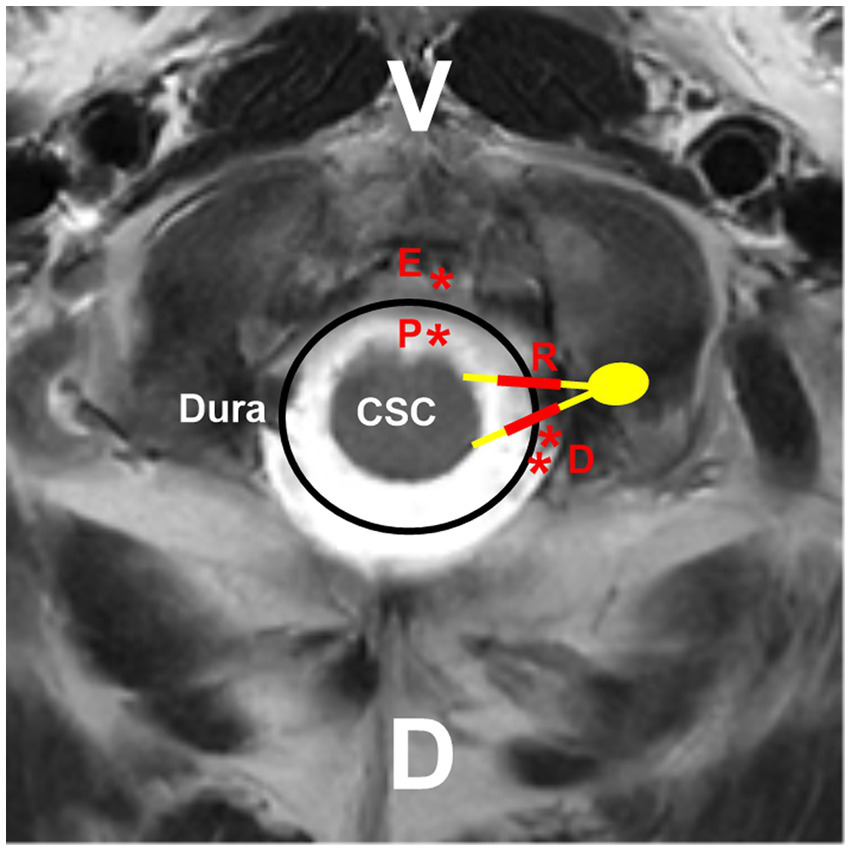

High cervical CCJ AVFs can be located on the inner or outer surface of the dura mater, on the spinal nerves, or on the spinal cord surface and can be divided into the following four types: DAVFs, radicular AVFs (RAVFs), epidural AVFs (EAVFs), and perimedullary AVFs (PAVFs) (Figures 4, 5), in which DAVFs and RAVFs tend to occur at the C1 level and EAVFs and PAVFs tend to occur at the C2 level (10, 33, 53, 54).

Figure 4

Locations of different high cervical CCJ AVFs. On the hybrid mode pattern of magnetic resonance imaging, the locations of different high cervical CCJ AVFs are shown. PAVF (red P with asterisk) located at the ventral spinal cord surface, RAVF (red R with thick line segments) located at C1-C2 nerves, DAVF (red D with double asterisks) located at the dorsal dura, EAVF (red E with asterisk) in ventral epidural space. AVF, arteriovenous fistula; C1-C2, first and second cervical vertebrae; CCJ, craniocervical junction; CSC, cervical spinal cord; D, dorsal; DAVF, dural AVF; EAVF, epidural AVF; PAVF, perimedullary AVF; RAVF, radicular AVF; V, ventral.